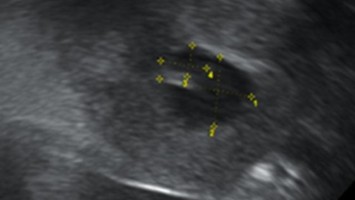

Was ist die Ursache für die Schmerzen im Unterbauch?

Ein 10-jähriges Mädchen in gutem Allgemeinzustand und altersentsprechender Entwicklung wurde aufgrund seit 4 Wochen bestehender und an Intensität zunehmender Unterbauchschmerzen zum Ausschluss eines entzündlichen Geschehens auf unsere Kinderstation aufgenommen. Mittels Bildgebung kamen die Ärzte der Ursache auf die Spur.